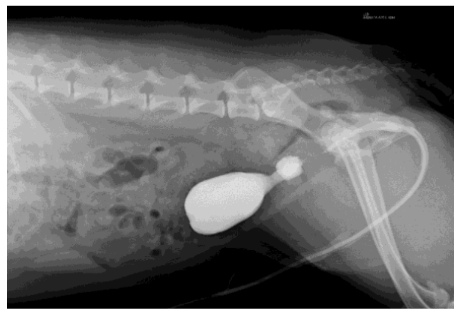

Com auxílio da ultrassonografia transoperatória, foi identificado que os cálculos haviam migrado ao interior da lesão prostática, portanto, foi realizado tentativa de hidropulsão através do catéter uretral na tentativa de retorná-los à vesícula urinária, mas sem sucesso com a técnica. O paciente foi então encaminhado para a realização de exame de Uretrocistografia Retrógrada, para confirmar a suspeita levantada de ruptura de uretra em sua porção prostática.

Para a realização do exame contrastado, foi administrado através do catéter uretral o contraste iodado Omnipaque® na dose de 6 ml/kg, diluído na proporção de 1:1 em solução fisiológica seguido da realização de radiografias abdominais sequenciais imediatas e após 5 minutos da administração do contraste.

Através da Uretrocistografia Retrógrada foi visualizado um ponto de extravasamento de contraste para a cavidade abdominal advindo de uretra prostática, porém ainda havendo repleção da vesícula urinária pelo contraste, o que indicava que havia uma ruptura uretral, mas que esta seria parcial.

Diante de todo o quadro, a princípio optou-se pela tentativa de tratamento conservativo, acompanhando através de exames de imagem a cicatrização da uretra, mantendo o paciente em regime de internação e com catéter uretral fixado para esvaziamento da vesícula urinária, controle de débito urinário e impedir a ocorrência de retardo na cicatrização pela contaminação por urina.